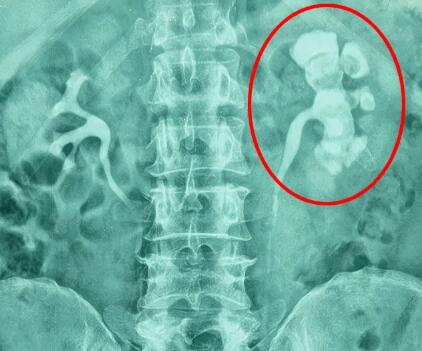

在泌尿外科的常见疾病里,肾结石绝对是个“常客”。可别小瞧它,临床数据显示,肾结石的发病并非随机,而是在特定人群中扎堆出现。那么,究竟哪些人更容易被肾结石“盯上”呢?

结合《中国泌尿外科疾病诊断治疗指南(2023版)》和临床经验,下面这6类高风险人群可要注意啦!